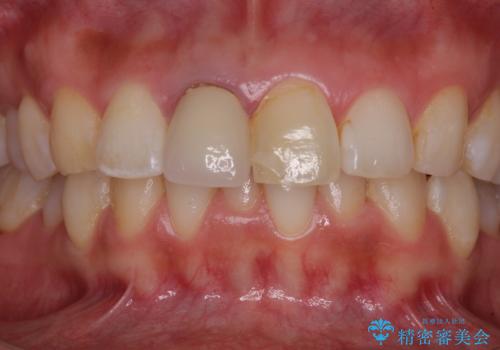

目立つ前歯の詰め物 オーダーメイドのセラミッククラウンで審美的に仕上げる

2本同時に処置をし、2本とも明るい色合いにすることをお勧めしましたが、今回は1歯のみとしました。

左右のバランスが取れ、患者様には大変満足していただきました。